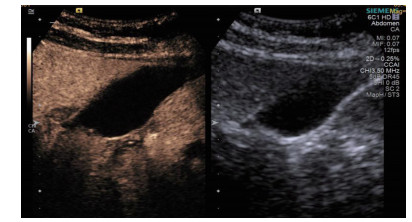

| 图 2 穿刺后经引流管超声造影,显示置管路径(箭头处) |

术后再次经肘静脉超声造影同时经引流管超声造影:PTGBD后,再次经肘静脉快速团注SonoVuel 2 mL,在造影成像模式下进行观察肝脏被膜、胆囊床穿刺路径有无造影剂外渗,腹腔内有无外渗凝聚的造影剂,判断有无活动性出血及出血程度,如判断出血速度快、出血量较大,考虑动脉性出血,及时改为开腹或腔镜手术止血。PTGBD术后经引流管超声造影,置管成功后快速抽出胆囊内残留胆汁,减轻胆囊压力后,在超声造影模式下直接经引流管注入配制待用的稀释声诺维造影剂20 mL,实时动态的观察造影剂在胆囊腔内的充盈范围(图 2、3),评估引流管的通畅程度及引流范围、观察其在胆囊腔内的位置走形及卷曲情况、观察胆囊周边及腹腔内有无造影剂外渗。如患者腹痛症状加剧,结合经引流管超声造影判断有胆汁漏出表现,应持续监测观察患者生命体征及保守治疗效果,必要时及时改行开腹或腔镜手术治疗。

超声造影是利用超声造影剂微泡(本组应用的是声诺维超声造影剂微泡)在低机械指数声波照射下发生共振,产生线性及非线性谐波回声信号,形成造影增强图像的技术,是近年来新兴的超声技术,具有实时、可连续观察、无辐射、可重复性好、毒不良反应少等优势,为临床提供了全新的诊疗手段[14]。经肘静脉注入的标准配置超声造影剂是一种血池造影剂,可以反映组织的血流灌注情况同时亦被广泛应用于肝、脾、肾等实质性脏器破裂的诊断,其诊断的敏感性及特异性均明显优于二维超声,且与增强CT有较好的一致性[15-16]。本组病例术前经肘静脉注入标准配置造影剂后,胆囊壁均显影增强,胆囊穿孔及周边积液处表现为造影无充盈区,穿刺置管后再次静脉路超声造影,迅速发现术后出血部位且可敏感评估是否为活动性出血(经手术证实)。除1例因活动性出血中转腹腔镜手术外,其余32例置管成功后经引流管口注入稀释造影剂20 mL(1:200稀释),评价引流管位置、引流范围及是否出现胆汁外漏取得良好效果,所有引流导管均能够清晰显示引流导管置入路径、引流管形态及引流范围,引流管置入恰当者,头端位于胆囊内,全管显影清晰,造影剂弥散区域与胆囊大小吻合; 置管后胆汁漏出者,可见造影剂沿引流管周边渗出[17-18],本组中3例出现造影剂外渗,其中两例渗出范围局限于胆囊床附近,未渗出至游离腹腔,患者腹痛症状稍有加剧,经胆囊减压及对症处理后好转,其中1例见造影剂渗出至肝肾间隙,患者腹痛症状加剧明显,考虑置管位置不当,余行急诊腹腔镜手术治疗,术中证实为系膜胆囊,且可见引流管侧孔部分外露。笔者的经验是,术前选择静脉路超声造影有助于对胆囊情况的评估及穿刺点的选择,术中正确选择穿刺针的入路有利于提高穿刺引流的成功率。首先是胆囊穿刺部位的选择应选择在靠近胆囊颈侧,此处胆囊位置比较固定,受体位影响较小,且胆囊床结缔组织较为固定,有助于将漏出胆汁包裹局限,其次是进针方向与胆囊床尽可能保持垂直,减少进针位置的偏移,同时置管成功后应即刻尽量抽尽胆囊内的感染性胆汁,生理盐水冲洗后行经引流管稀释超声造影有助于判断置管位置、引流范围及是否出现胆汁漏出,减少不必要的并发症发生率。穿刺引流后可以根据患者的营养状况待窦道形成稳定后择期拔除引流导管。对全身情况改善适合手术治疗且有手术意愿者可以考虑择期胆囊切除术。